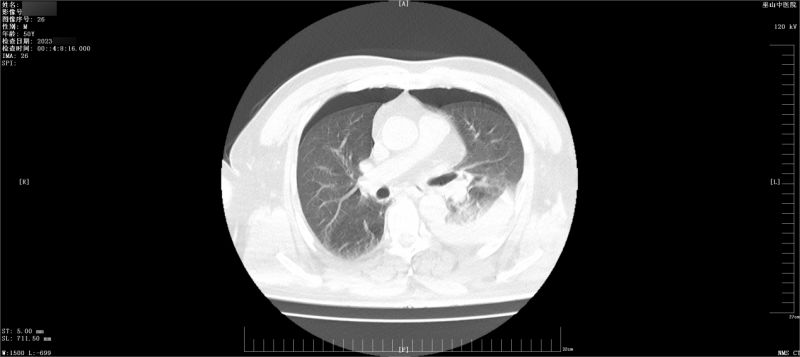

当日凌晨,该伤者因刺伤胸部、腹部2小时后紧急入院。入院时,精神差,面色苍白,呈急性疼痛面容,全身血污。体温35.9℃,脉搏154次/分,呼吸28次/分,血压86/60mmHg。双侧后胸部第五肋间可见各一处2.5cm锐器伤口,有鲜血及气泡溢出,左上腹部纵向伤口长约2.5cm,深入腹腔,有鲜血溢出。入院急诊CT检查提示:双侧血气胸,左侧为重,腹部脐上左腹壁贯穿伤,腹腔盆腔积液,腹腔积气。

由于病情危重,在急诊科建立静脉通路,并完成CT检查后,该伤者被送到手术室,接受抗休克抢救治疗及下一步的手术治疗。在与患者家属沟通后,在气管插管全麻下,医生行剖腹探查术+空肠破损修补术+腹腔冲洗引流术+大网膜部分切除术+胸腔镜下左侧胸腔内血肿清除+肋间血管破裂止血+肺裂伤修补术+右侧胸腔闭式引流术,在外科团队及各科室的密切配合下,手术顺利完成,患者脱离危险,术中患者的胸腔及腹腔出血共计2500ml。术后,伤者生命体征逐渐平稳且恢复良好,并于日前痊愈出院。